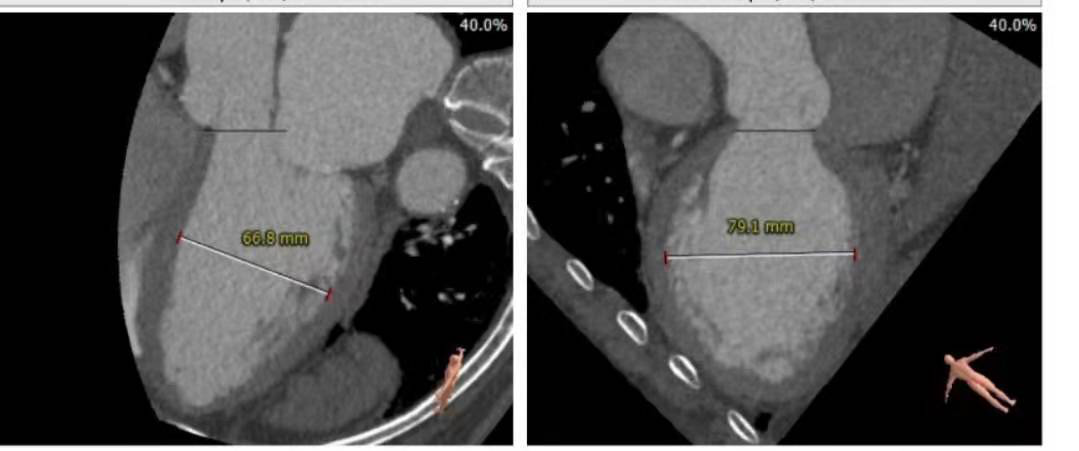

术前分析及手术策略

瓣环直径26.7

左室流出道直径:30.8

升主动脉增宽

冠脉高度尚可。左冠高度:13.4,右冠高度:20.6。心脏角度52

心室较大,心尖超薄

入路粗稍弯曲

1. 瓣膜型号及球囊:瓣环26.7mm,左室流出道30.8mm,考虑32VenusA Plus瓣膜,

2. 冠脉风险:结合窦部大小大,stj高度和直径,冠脉风险小

3. 释放体位:结合瓣膜位置要求高,瓣膜下移风险大,故选择稍高1-2mm释放

4. 入路情况:入路直径较粗,稍弯曲,右股作为主入路

5.其他风险:心脏角度偏横位心,升主增宽,增加过弓难度,置入输送器时可调整超硬导丝调整方向延小弯侧方向靠。心尖较薄注意超硬导丝塑形防止心尖穿孔。